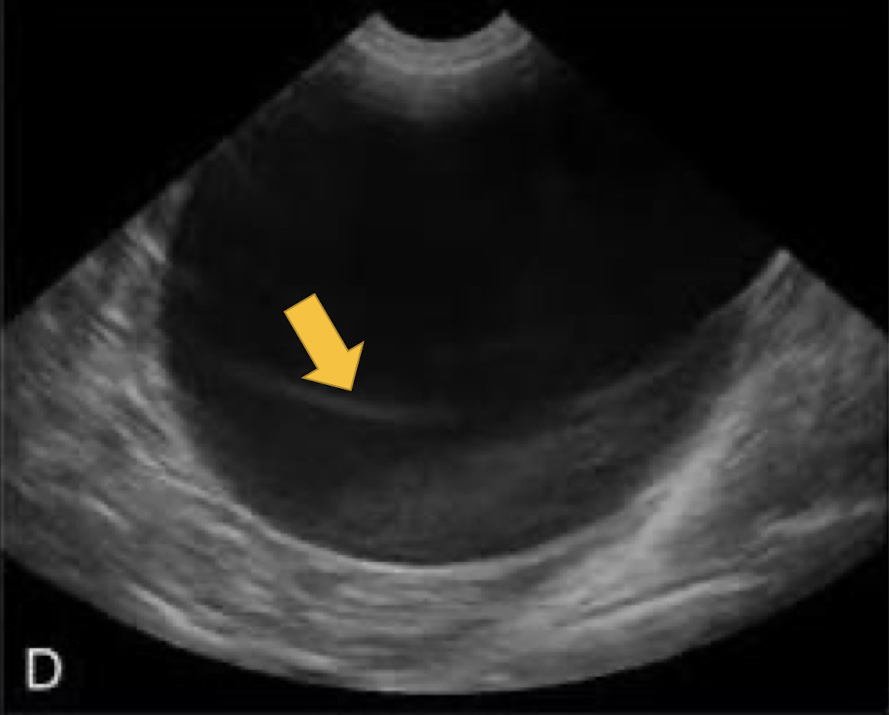

artifact that occurs when imaging a 3D structure with anechoic fluid

slice thickness artifact

What artifact is this showing?

Where would a slide thickness artifact be most commonly found?

bladder and gall bladder (artificial sludge)